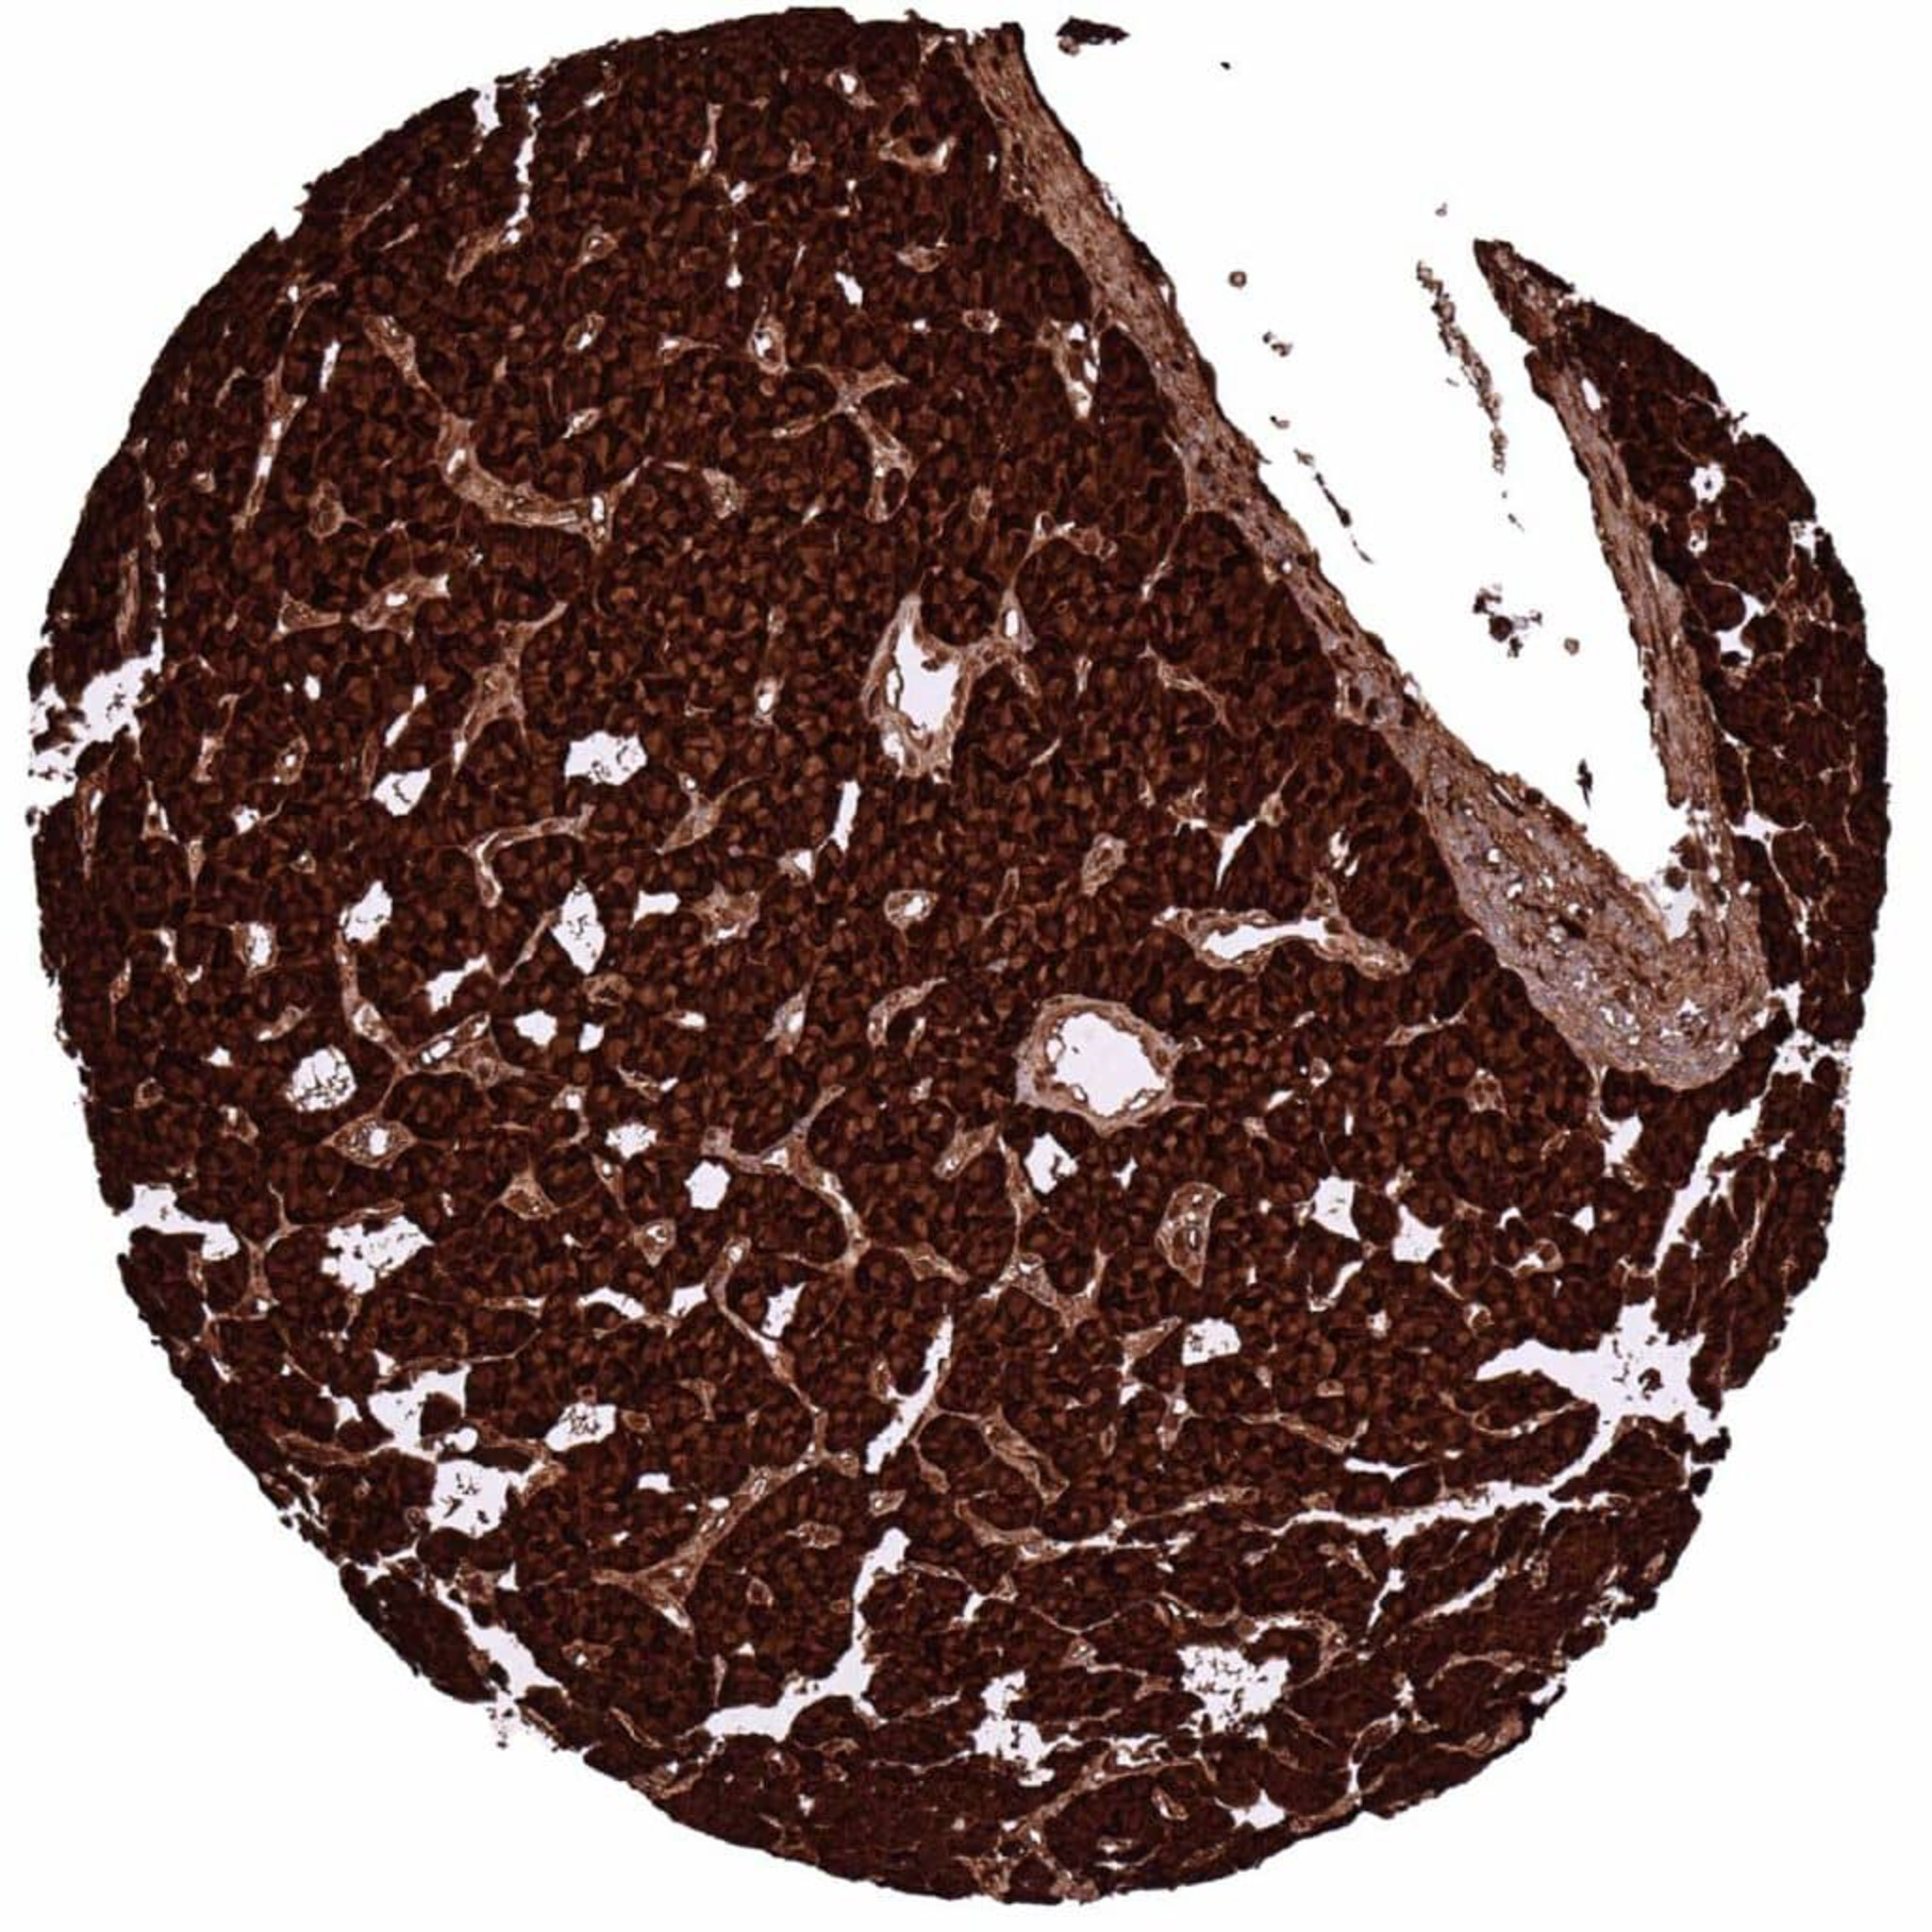

Pancreas – Neuroendocrine tumor (Insulinoma) with strong C-peptide immunostaining of tumor cells

Pancreas – Neuroendocrine tumor (insulinoma) with strong C-peptide positivity of tumor cells

Pancreas – Neuroendocrine tumor (insulinoma) with strong C-peptide staining of all tumor cells